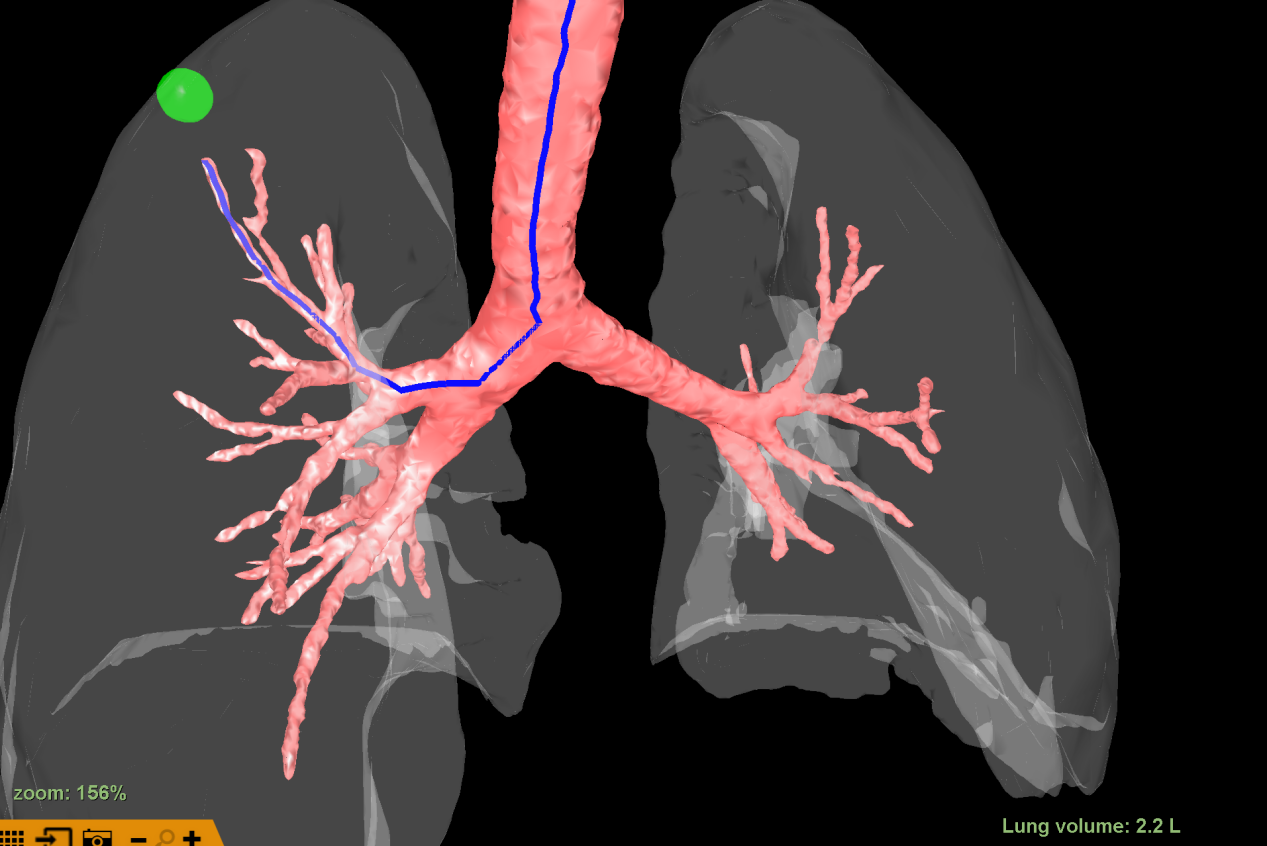

该病灶于右肺上叶尖段可见一磨玻璃结节,结节较小,且位置极高,常规器械滑行或手指触摸定位结节难度较大,为达到精准定位、精准治疗,且有效缩短患者手术时间目的。朱坤寿主任医师及林绍峰副主任医师术前充分讨论,利用Lungpro增强现实支气管导航术前三维重建支气管树,分析病灶与气道位置关系,拟定染色标记胸膜区域。

三维支气管树重建